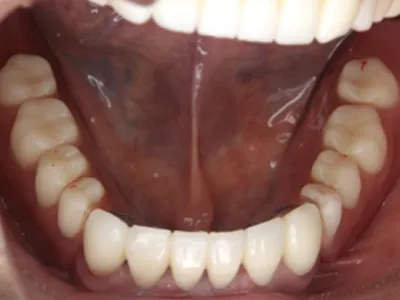

after

主訴入れ歯がくちゃくちゃして噛めない

治療内容被せ物(メタルボンド)保険外の義歯(ミリングギシ)

治療期間1年

費用1,100,000円(税込)(義歯と被せ物代合わせて)

リスク・副作用義歯なので着脱が必要です。仮の義歯を作る場合があります。